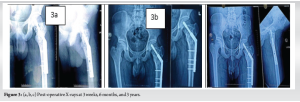

A 16-year-old male presented to the outpatient department with a 3-year history of persistent pain in the proximal left thigh, following a fall from height sustained at that time. He experienced gradually progressive pain, dull aching in character, non-radiating, aggravated on walking/weight bearing, relived after rest or taking analgesics. A physical examination revealed no evident abnormalities, with the exception of tenderness over the proximal thigh. Radiographic picture showed well-defined expansile lesion with thin cortex, multi-lobulated soap bubble appearance, with loss of corticomedullary differentiation, no periosteal reaction, extending from base of neck up to the proximal femur (Fig. 1). The whole-body skeletal survey did not show similar lesion elsewhere in the body. The initial diagnosis at admission was of a bone cyst, based on radiological evidence, that revealed a well-defined cortical rim was noted with soft tissues component within and lesion was approximately 29.4 × 36.6 mm on non-contrast computed tomography (CT) left femur (Fig. 2). The patient underwent extended curettage with Bone graft, bio composite augmentation and DHS fixation of left hip Joint (Fig. 1). Histological examination revealed hypocellular stroma composed of mature bland fibroblasts separated by abundant collagen without nuclear atypia. In addition, there was no necrosis (Fig. 4). Thus, based on the postoperative analyses and histological report, a diagnosis of DF was determined. The patient was advised to remain on bed – rest for 3 months, and then partial weight – bearing was allowed. The patient was followed up every month for the first 6 months, then every 3 months physically and radiologically (Fig. 5). At 3-year follow-up, there was no disability or local recurrence or distant metastasis (Fig.5).